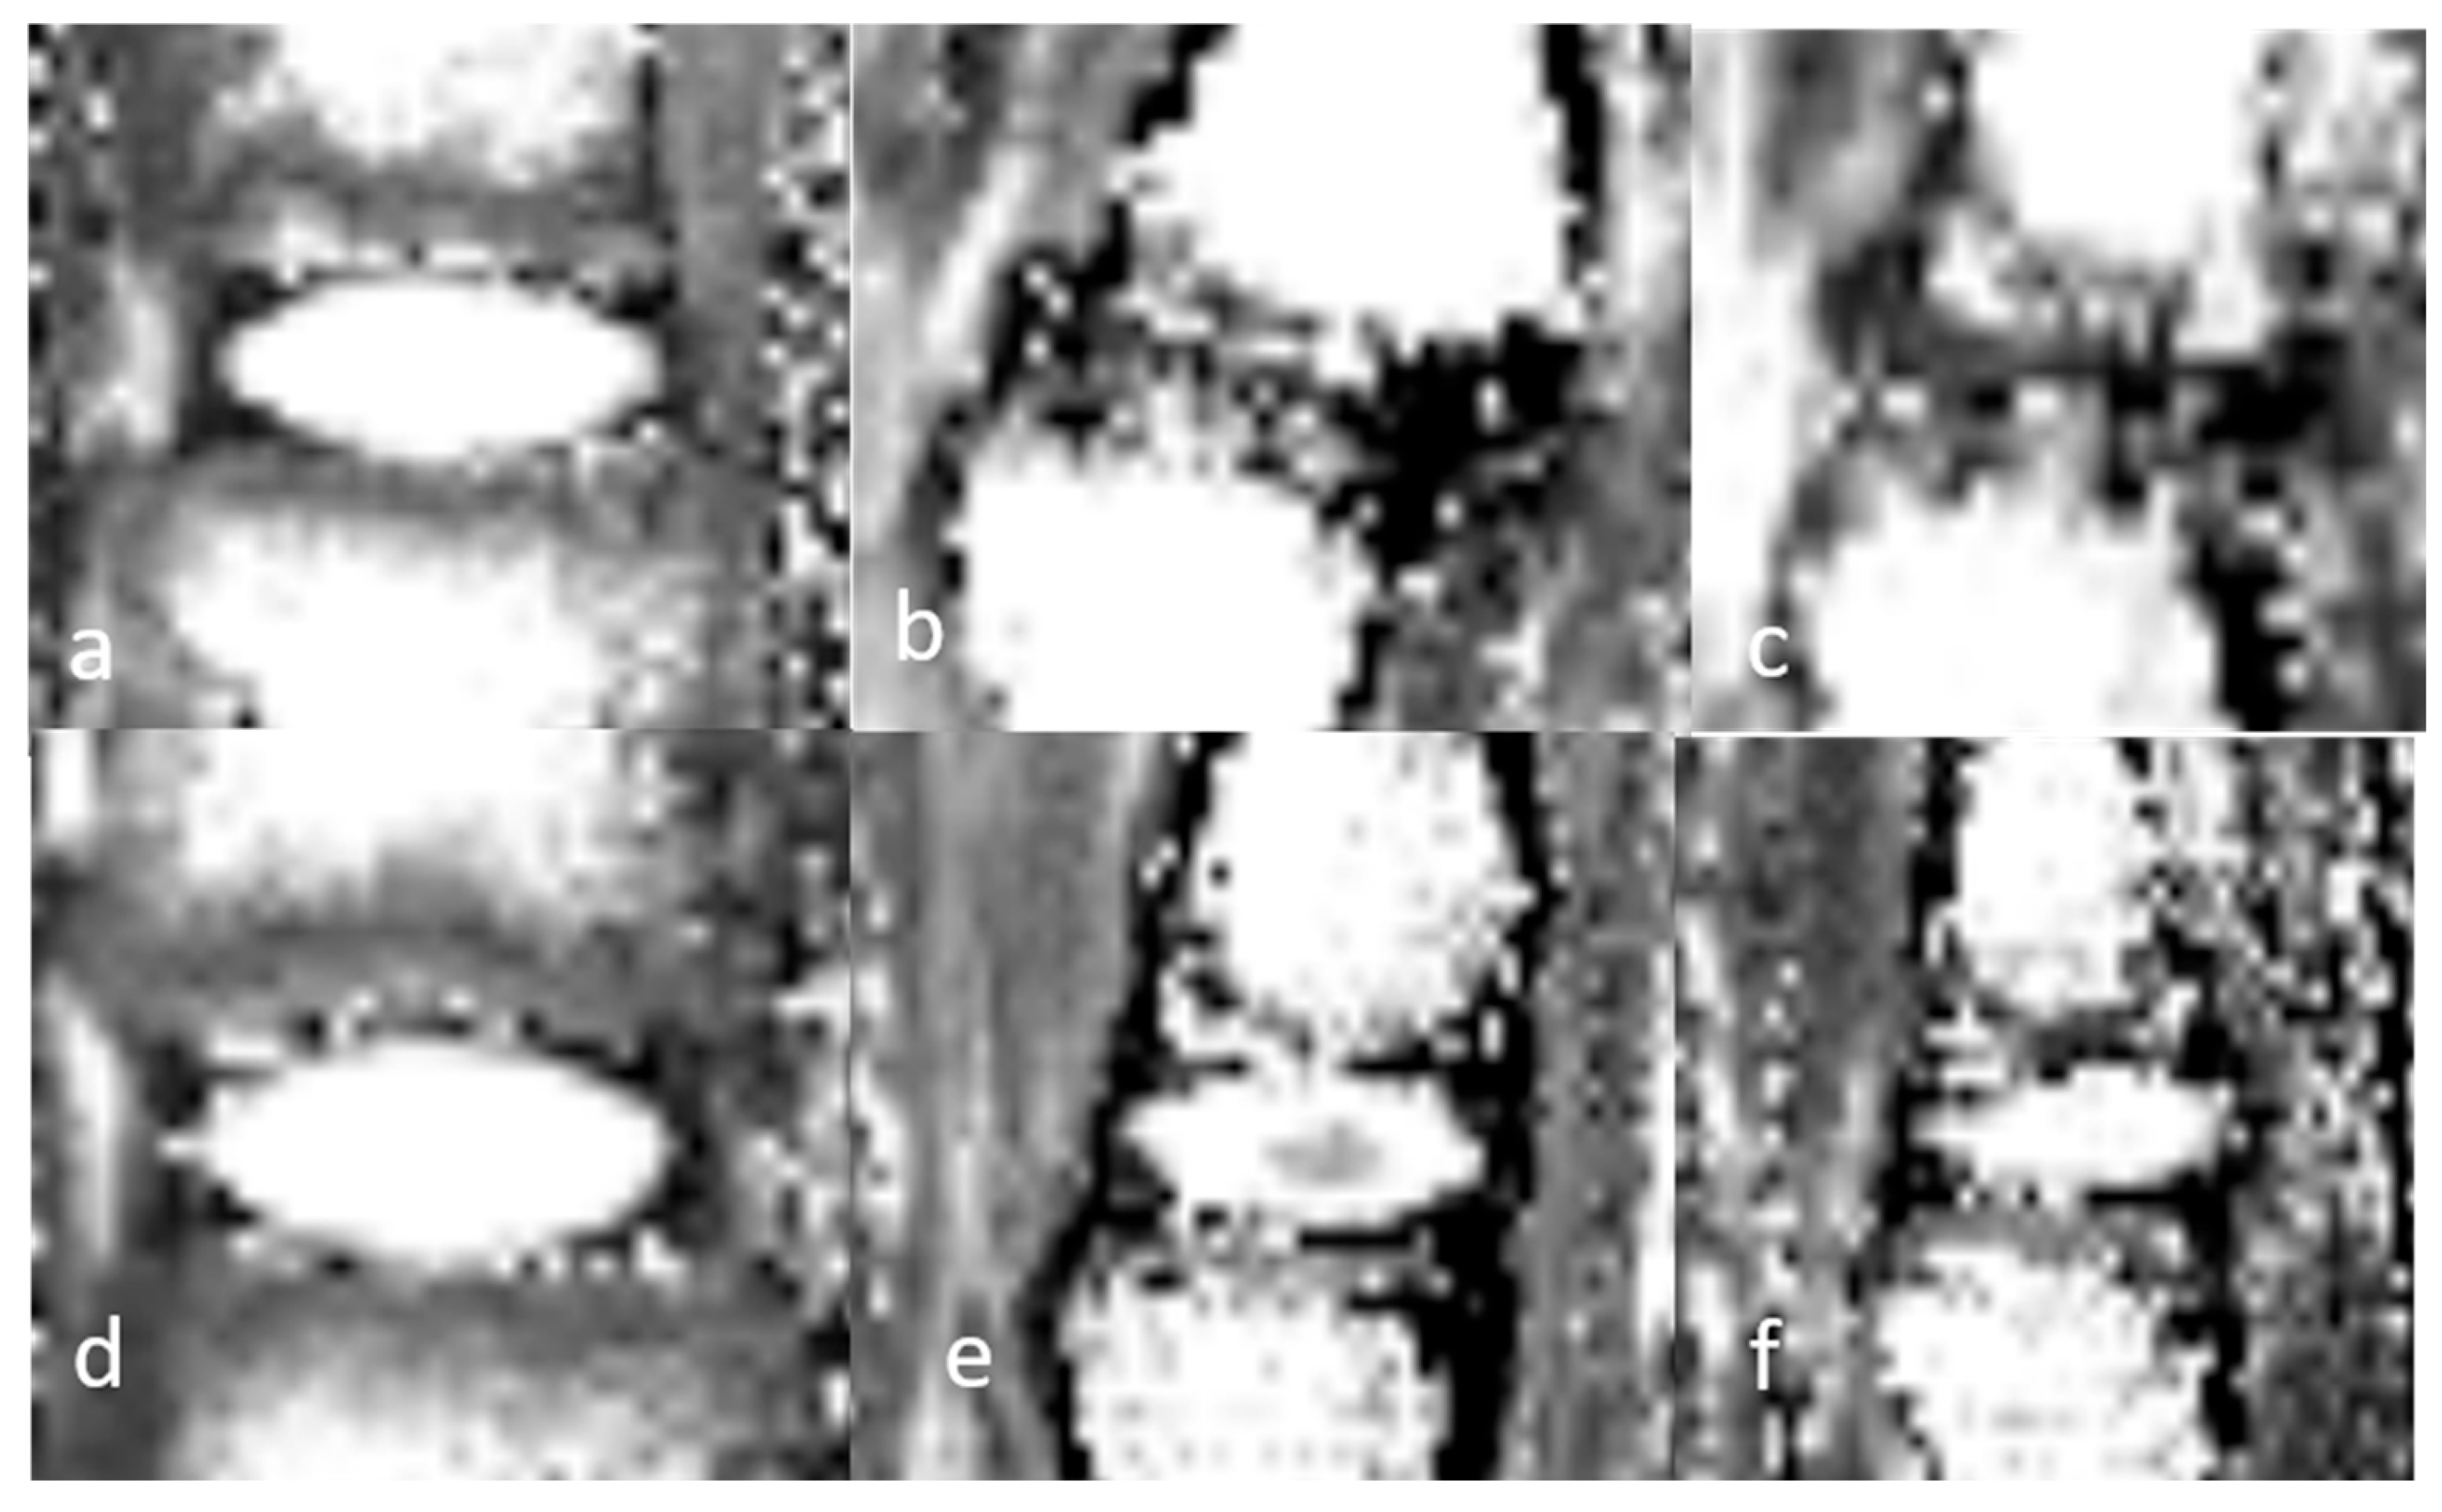

3.1. Image Analysis

3.1.3. Quantitative Analysis of the Normal DVC (Table 4)

3.1.4. Quantitative Analysis of the DVC in DDD Rats (Table 4)